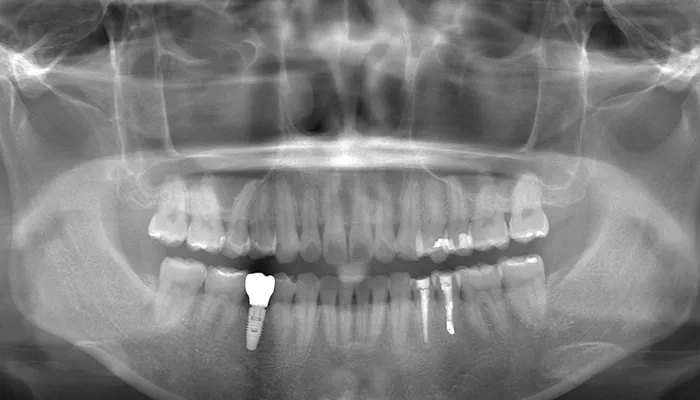

After

治療後の口腔内写真

術後の口腔内写真

右下5番のインプラントは良好に骨結合し、自然な形態と色調の補綴物を装着しました。

インビザライン矯正により歯列が整い、清掃性・咬合バランスともに改善しました。

ホワイトニングにより歯全体の色調が明るくなり、笑顔の印象が大きく改善しました。

患者様は審美性・機能性ともに大変満足していらっしゃいました。